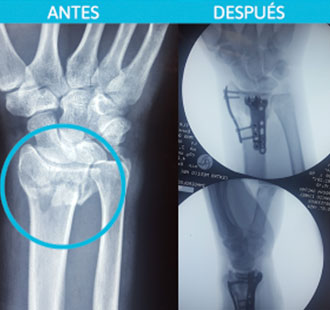

Fractura de la muñeca por caída. (Radio esta fragmentado).

Después: Fijación de cada fragmento para restituir anatomía y mecánica de la muñeca.